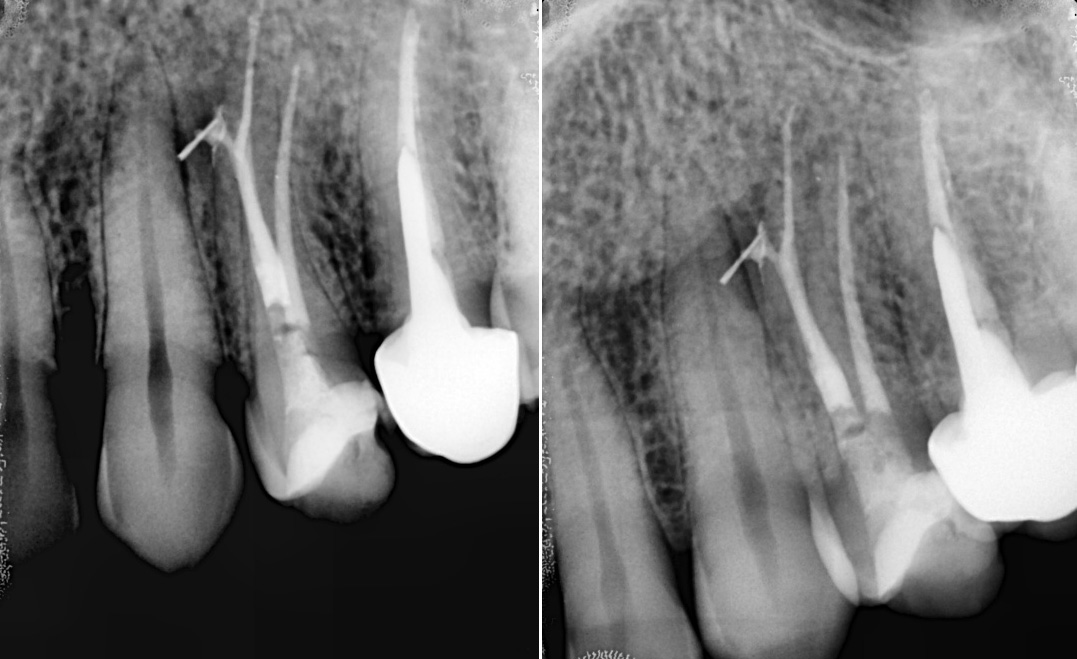

1-Year Follow-Up showing the complete healing of the periapical lesion on teeth #11 and #12

Tooth #11 with a calcified canal following traumatic injury

Cervical Radicular Perforation: Case Report

Does Endodontic Treatment with Bioceramic Cements Accelerate the Recovery of Periapical Lesions? A Case Report

BIO-C® TEMP: A new alternative for intracanal medication

Treatment of chronic apical abscess

Tooth Apexification Using Bioceramic Materials

The use of MTA-based endodontic cements in root perforation treatment

Endodontic retreatment with root perforation using MTA repair cement and MTA based sealer

Apical abces in one visit treatment

Endodontic treatment as a treatment for sinusitis of odontogenic origin

Strategies for endodontic retreatment